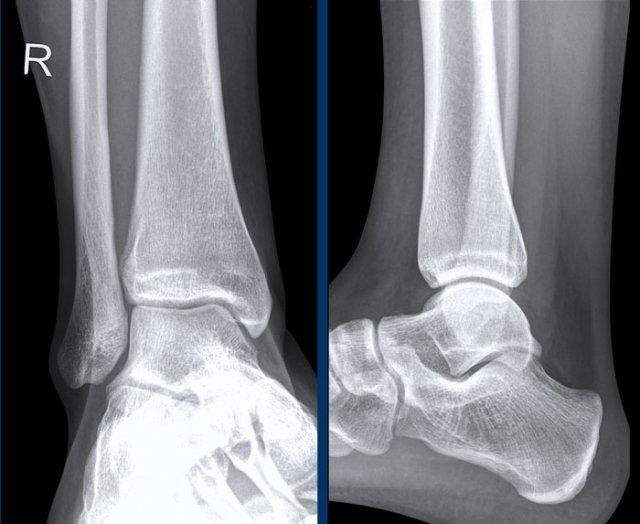

Ca 1 – Chấn thương cổ chân

Hình ảnh cho thấy những dấu hiệu gì và có ý nghĩa như thế nào?

Nhấp vào hình ảnh để xem phóng to.